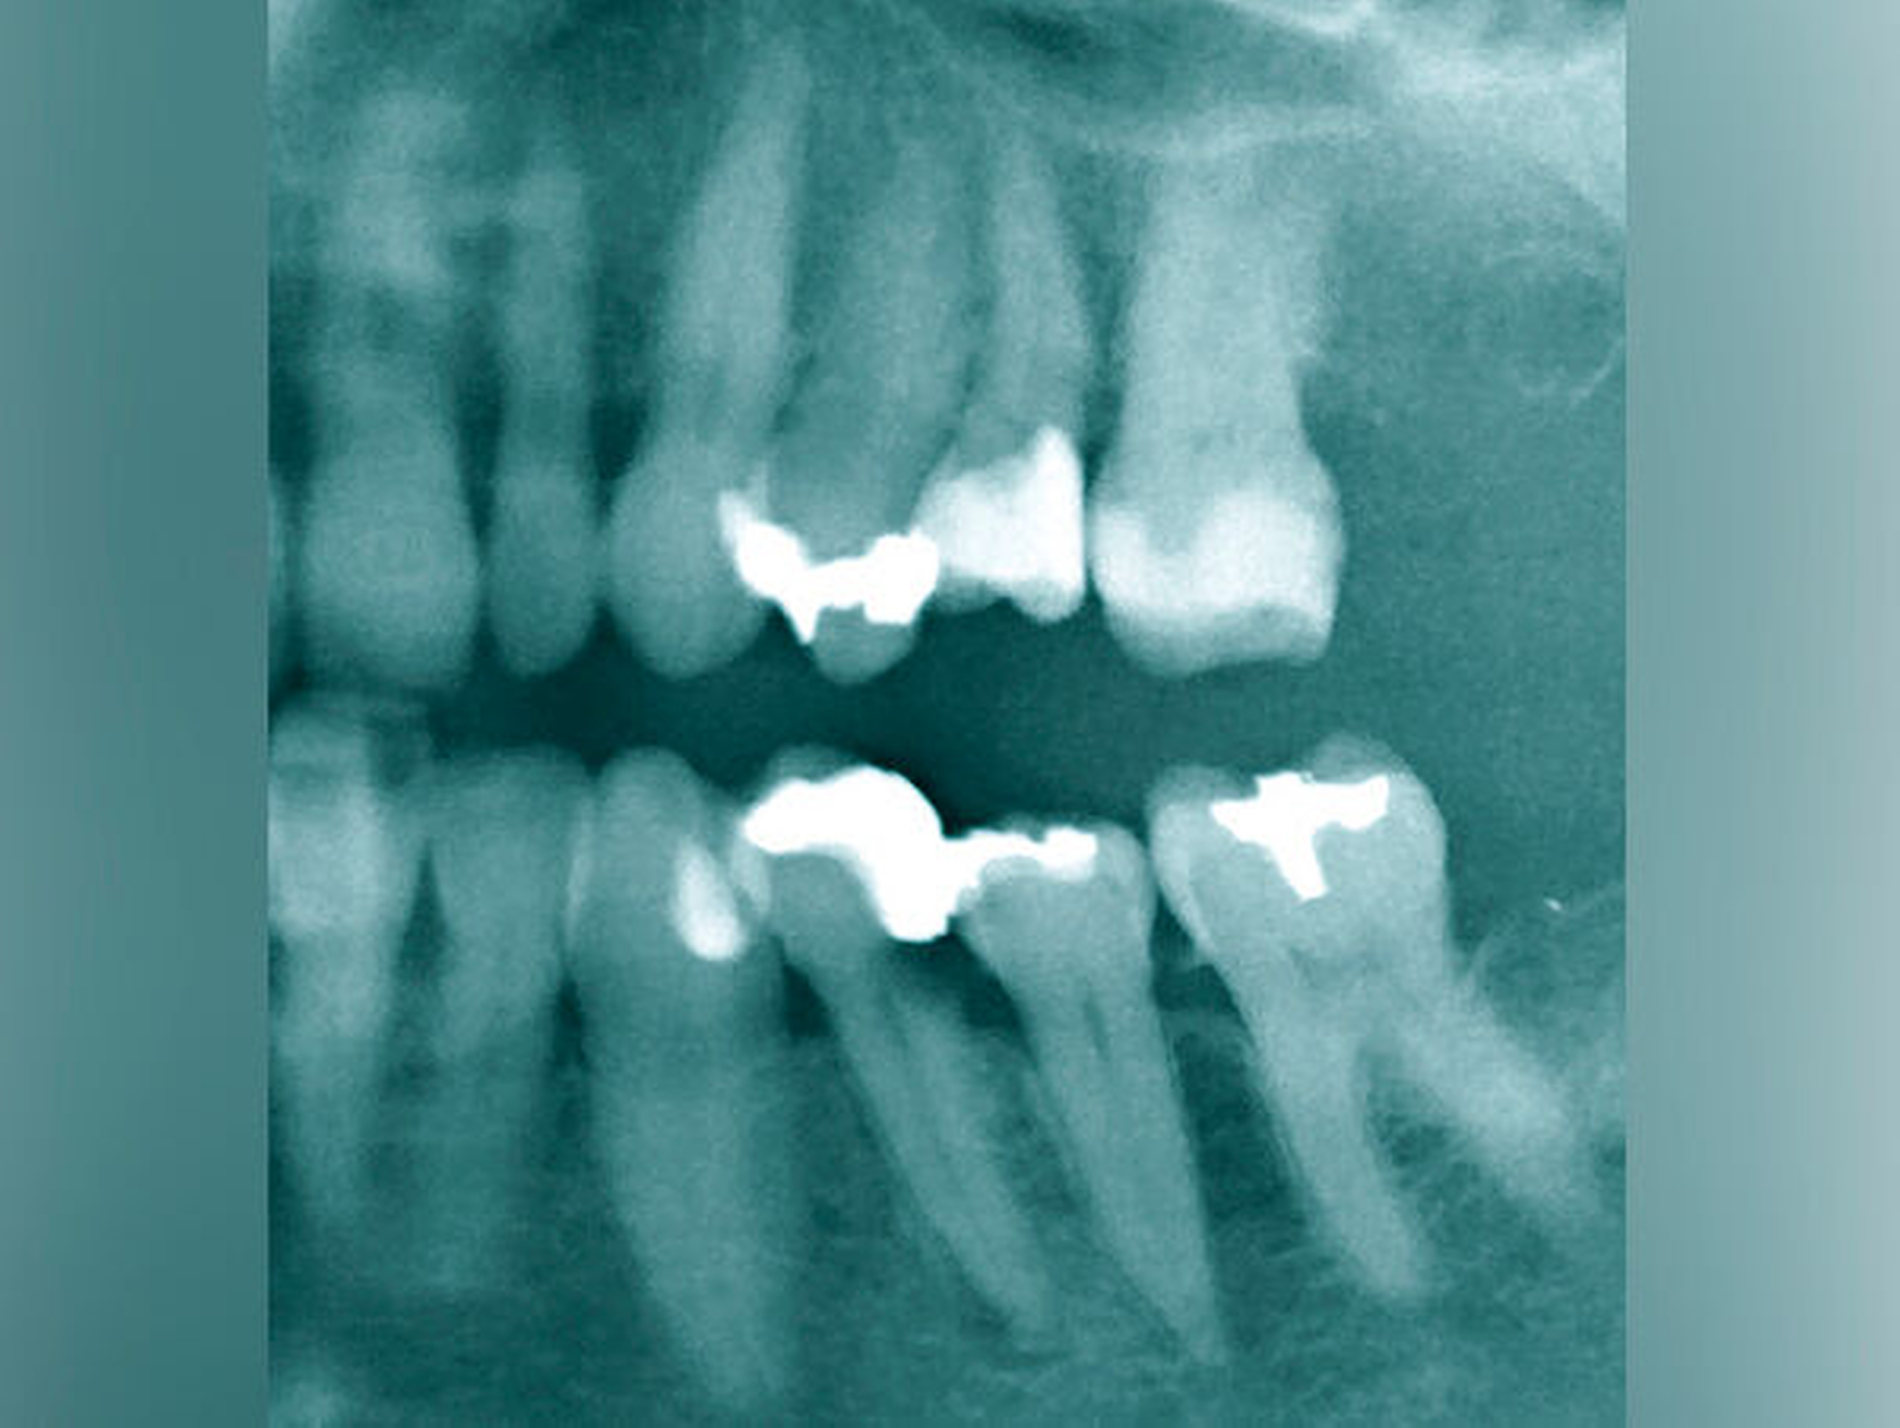

Der Patient stellte sich mit seit mehreren Tagen fortbestehenden starken Schmerzen im linken Ober- und Unterkiefer vor, die spontan auftraten und durch keinen Reiz ausgelöst werden konnten. Die Schmerzen waren nicht eindeutig einem Zahn zuzuordnen. Anamnestisch gab der Patient zusätzlich eine medikamentös eingestellte Hypertonie und Schilddrüsenunterfunktion an. Während der klinischen Inspektion und Palpation fiel eine diskrete Rötung und Schwellung Regio 34/35 auf. Der Perkussions- und Palpationsbefund für Zahn 34 war positiv. Differenzialdiagnostisch konnten die Zähne 25 und 26 mit ausgedehnten Füllungen als schmerzverursachende Zähne ausgeschlossen werden. Auf der OPG-Aufnahme war am Zahn 34 eine profunde Sekundärkaries am distalen Füllungsrand zu erkennen. Die apikale Aufhellung an Zahn 34 ließ eine infizierte Pulpanekrose vermuten (Abbildung 12).

Der Schwierigkeitsgrad entspricht dem Grad II. Sowohl in der Diagnostik als auch in der Therapie liegen erhöhte Anforderungen vor. Der Allgemeinzustand, die verringerte Compliance, die eingeschränkte Mundöffnung und das erschwerte intraorale Röntgen ließen bereits im Verlauf der Befundaufnahme eine größere Schwierigkeit erkennen. Die Wurzelspitze ist stark nach mesial gekrümmt. Der sehr kleine Krümmungsradius kann eine Instrumentenfraktur begünstigen. Die Bedingungen für einen aseptischen Zugang unter Kofferdam lagen nicht vor, so dass vorbereitend eine Kariesentfernung und eine dentinadhäsive präendodontische Restauration erforderlich wurden (Abbildungen 13a und 13b).